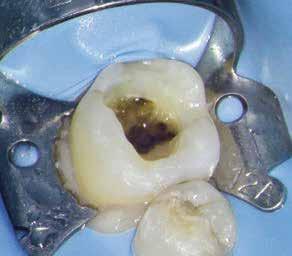

Gyökérkezelés

A gyökércsatorna-rendszer gyökértöméssel való zárása során elengedhetetlen a csatornák mindhárom dimenzióban való kitöltése. Ennek a követelménynek a guttapercha és eugenolalapú sealerek alkalmazásával járó hagyományos obturációs technikák választása esetén rendkívül nehéz eleget tenni, mivel ezekben az esetekben nem alakul ki adhézió a gyökércsatornák falai és a gyökértömésre használt anyagok között, valamint

ezek az anyagok képtelenek a gyökércsatorna-rendszer belső anatómiáját teljes mértékben feltölteni. A bioaktív kalcium-szilikát alapú anyagok a fizikokémiai tulajdonságaiknak köszönhetően képesek ezeknek a kihívásoknak eleget tenni.11 Ezek a sealerek elsősorban kalcium-szilikátot, cirkónium-dioxidot,

tantál-oxidot, kalcium-foszfátot és egyéb töltőanyagokat tartalmaznak.12 Alkalmazásuk során az egy poén technika (single cone technique) használatát javasolják. Ezt az eljárást ebben az esetben általában hidraulikus kondenzációs technikának nevezik. Ez a módszer képes a gyökértömés elkészítésének

Esetbemutatás (2., 3.)

Mindkét esetben irreverzibilis pulpitis miatt vált szükségessé a fogak endodonciai kezelése (6. a-d. és 7. a-b. ábrák). Az esetek ellátása során mindvégig minimálinvazív megközelítést alkalmaztunk. A hozzáférési nyílás kialakításától kezdve az endodonciai kezelés befejezését követő csonkfelépítésig, minden beavatkozás ennek megfelelően történt.

A konzervatív módon kialakított hozzáférési nyíláson keresztüli végzett kezelések során az egyik legnagyobb kihívást a gyökértömés elkészítése jelenti. Az egyenes irányú hozzáférés hiánya, a korlátozott rálátás és a pulpakamra kisméretű hozzáférési nyílása miatt csökkent hatékonyságú tisztíthatósága mind olyan faktorok, amelyeket figyelembe kell venni, ha minimálinvazív hozzáférést alakítunk ki.15 A kalcium-szilikát alapú sealerek fizikai tulajdonságai lehetővé teszik a klinikusok számára, hogy leküzdjék ezeket az akadályokat. A viszonylag

egyszerű obturációs technika, az anyag viszkozitási tulajdonságai és a pulpakamra viszonylag egyszerű tisztíthatósága a kezelésünk prognózisának veszélyeztetése nélkül teszi lehetővé az endodonciai beavatkozások lehető legkonzervatívabb módon történő kivitelezését. A bemutatott esetek ellátása során az Aurum Blue rendszert (Meta Biomed) használtuk a gyökércsatornák megmunkálására, míg a gyökértömés elkészítése során hideg hidraulikus kondenzációs technikát alkalmaztunk a kalcium-szilikát alapú CeraSeal (Meta Biomed) sealer felhasználásával (8. ábra).